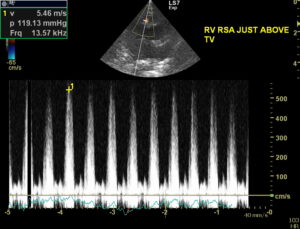

1 yr BSH, 4/6 murmur. Scan- normal LV, some RVH- annular FW and apically creating a DCRV effect (likely the source of the murmur). CFD- alias. in the RV extending apically. Unable to get good view of potential VSD. RSA- CWD produced a 5.4m/s velocity- poor angle for DCRV but good for a VSD. Slightly obliqued LSA may show VSD but may be the result of some color bleeding(hard to repeat). LPSLA aorta to Ruar/RA may show VSD near the last of the clip b/w LV and AO into RV? Suspect a restrictive VSD based on exam and echo. Recheck with better sedation scheduled. Thoughts? Thanks!!

Looks like a solid vsd to me but compensated. They can do well with these long term. Only slight rt vent thickening compensatory. I say let him be a cat and recheck in 6 mo:)